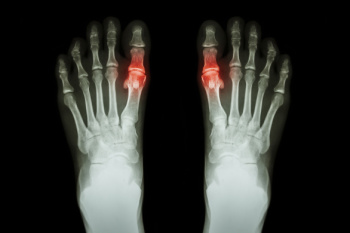

Gout is a form of arthritis that is caused by a buildup of uric acid crystals in the joints. This considered to be one of the most frequently recorded medical illnesses throughout history. Gout occurrences in the US have risen within the past twenty years and the condition now affects 8.3 million people which is 4% of all Americans. Researchers have found that gout affects men more than women and African-American men more than white men.

Symptoms of gout are warmth, swelling, discoloration, and tenderness in the affected joint area. The small joint on the big toe is the most common place for a gout attack to occur.

Gout is a form of arthritis that is characterized by sudden, severe attacks of pain, redness, and tenderness in the joints. The condition usually affects the joint at the base of the big toe. A gout attack can occur at any random time, such as the middle of the night while you are asleep.

- Intense Joint Pain – Usually around the large joint of your big toe, and it most severe within the first four to twelve hours

- Inflammation and Redness -Affected joints may become swollen, tender, warm and red